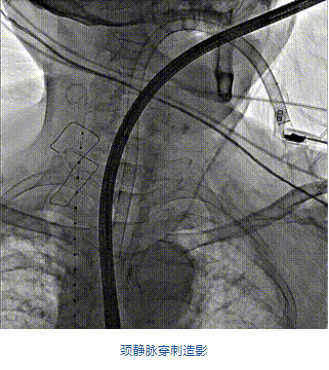

團隊前期經(jīng)過多次討論,制定了周密的手術(shù)策略和預(yù)案。由于患者已是近九旬的超高齡老人,傳統(tǒng)外科開胸手術(shù)風(fēng)險極高,純介入經(jīng)血管三尖瓣替換能夠明顯減少創(chuàng)傷。術(shù)中陳茂及馮沅教授結(jié)合體表定位在造影指示下精準(zhǔn)穿刺右側(cè)頸靜脈并預(yù)置兩把血管縫合器。成功建立經(jīng)皮血管入路后在食道超聲和DSA的引導(dǎo)下順利完成人工瓣膜植入,術(shù)后超聲和造影顯示人工三尖瓣同軸性良好,瓣架固定牢靠,無反流和瓣周漏,平均跨瓣壓差降為1mmHg。術(shù)畢收緊預(yù)置的血管縫合器縫線完成止血,縫合效果滿意,在手術(shù)室即刻拔除氣管插管。